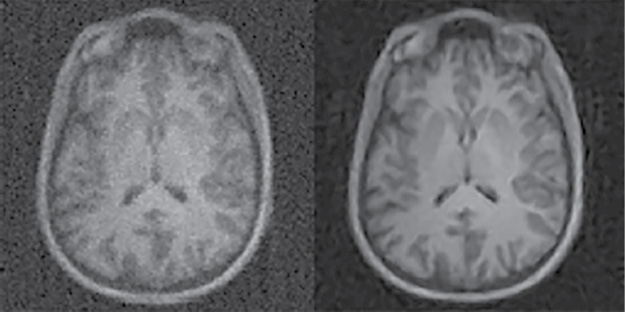

The performance boost provided by sensor-based AI is evident in the Automated Transform by Manifold Approximation, or AUTOMAP, an approach developed at Center for Biomedical Imaging at Massachusetts General Hospital, Boston. As outlined in a study published last year in the journal Nature, AUTOMAP uses deep learning (DL), a form of AI, to produce higher-quality MR images without having to collect additional data. The technique reconstructs the images extremely quickly, potentially providing real-time diagnostic information during the scan that would prevent additional visits.

Researchers trained AUTOMAP to learn the transformation between sensor and image domains using real-world images like cats, dogs, trees and houses — a process that study senior author Matthew Rosen, PhD, likened to teaching someone to paint by showing them pictures of the Mona Lisa alongside the paints on a palette. Dr. Rosen is the director of the Low-field MRI and Hyperpolarized Media Laboratory and the co-director of the Center for Machine Learning at the MGH Martinos Center.

“AUTOMAP is trained on pairs of example images and what they look like in the sensor domain,” Dr. Rosen said. “The network learns how to invert the forward-encoded relationship —something that can sometimes be mathematically very challenging — and once trained can reconstruct high-quality images directly from raw signal data from the scanner.”